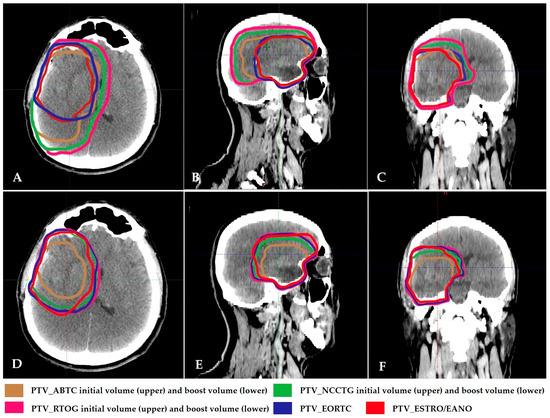

| Group | Definition | CTV-Initial | CTV-Boost | PTV |

|---|---|---|---|---|

| ABTC | Two-phase: 46 + 14 = 60 Gy | T2 + T1E + resection cavity + 5 mm | Resection cavity + T1E + 5 mm | 5 mm |

| EORTC | Single-phase | Resection cavity + T1E + 2 cm | - | 5 mm |

| NCCTG/Alliance | Two-phase: 50 + 10 = 60 Gy | T2 + T1E + resection cavity + 20 mm | Resection cavity + T1E + 20 mm | - |

| RTOG/NRG | Two-phase: 46 + 14 = 60 Gy | T2 +T1E + resection cavity + 20 mm | Resection cavity + T1E + 20 mm | 5 mm |

| ESTRO/EANO | Single-phase | Resection cavity + T1E + 15 mm (include non-contrast-enhancing tumor if suspected on FLAIR imaging) | - | 3 mm |